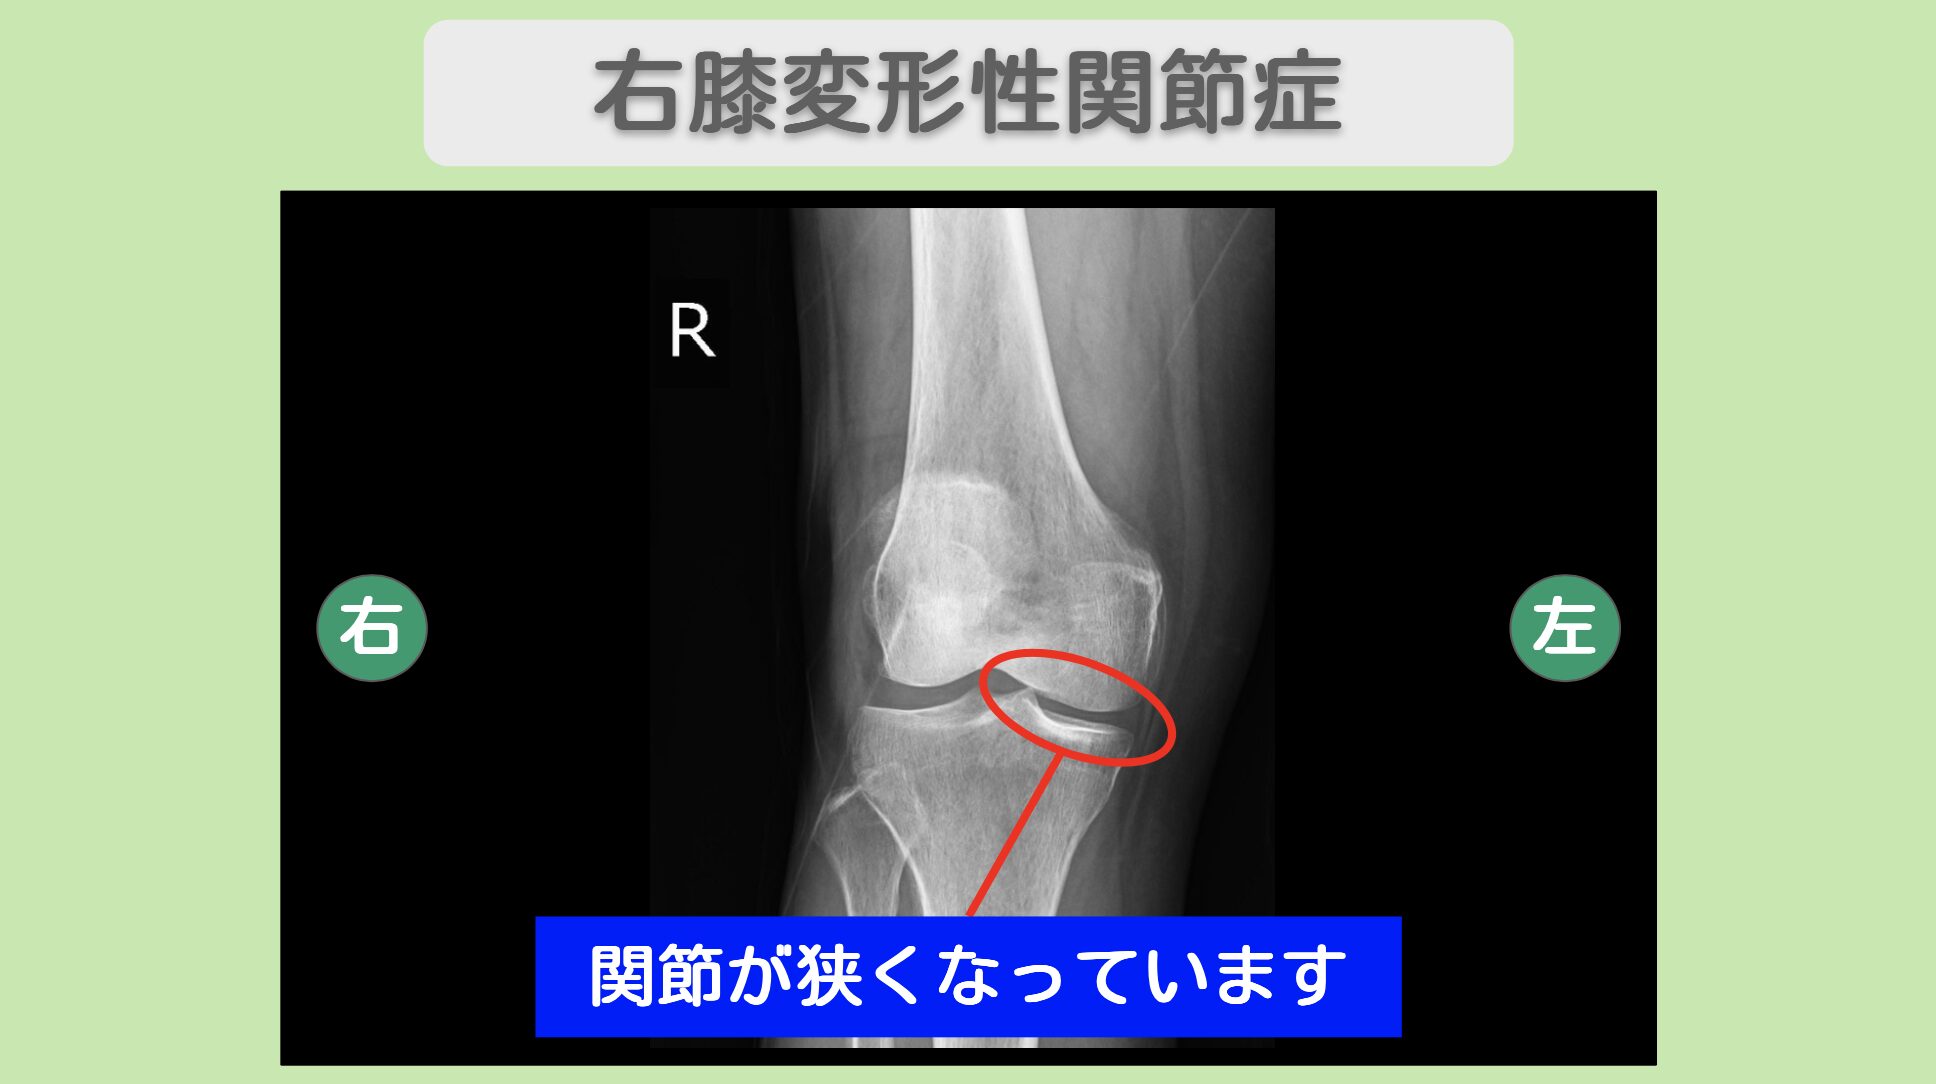

レントゲン所見

レントゲンにて関節の狭小化を認めます

レントゲン検査では、右股関節・右膝関節・右足関節のいずれにおいても軟骨のすり減りが確認されました。